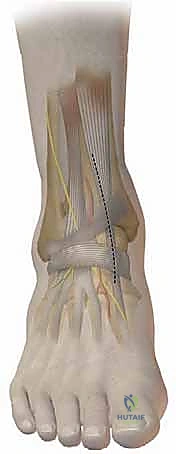

- التعقيم والشق الجراحي: يتم تعقيم الساق بالكامل. يُجري الجراح شقاً جراحياً دقيقاً في الجلد فوق منطقة الكاحل (الجانب الداخلي أو الخارجي حسب نوع القطع). يتم إبعاد الأنسجة الرخوة والأعصاب والأوعية الدموية بحذر شديد لحمايتها.

- قص العظم (Osteotomy): باستخدام منشار جراحي دقيق وموجهات خاصة، يتم قص عظم الظنبوب (وفي بعض الأحيان عظم الشظية أيضاً) بالزاوية التي تم تحديدها مسبقاً في التخطيط الثلاثي الأبعاد.